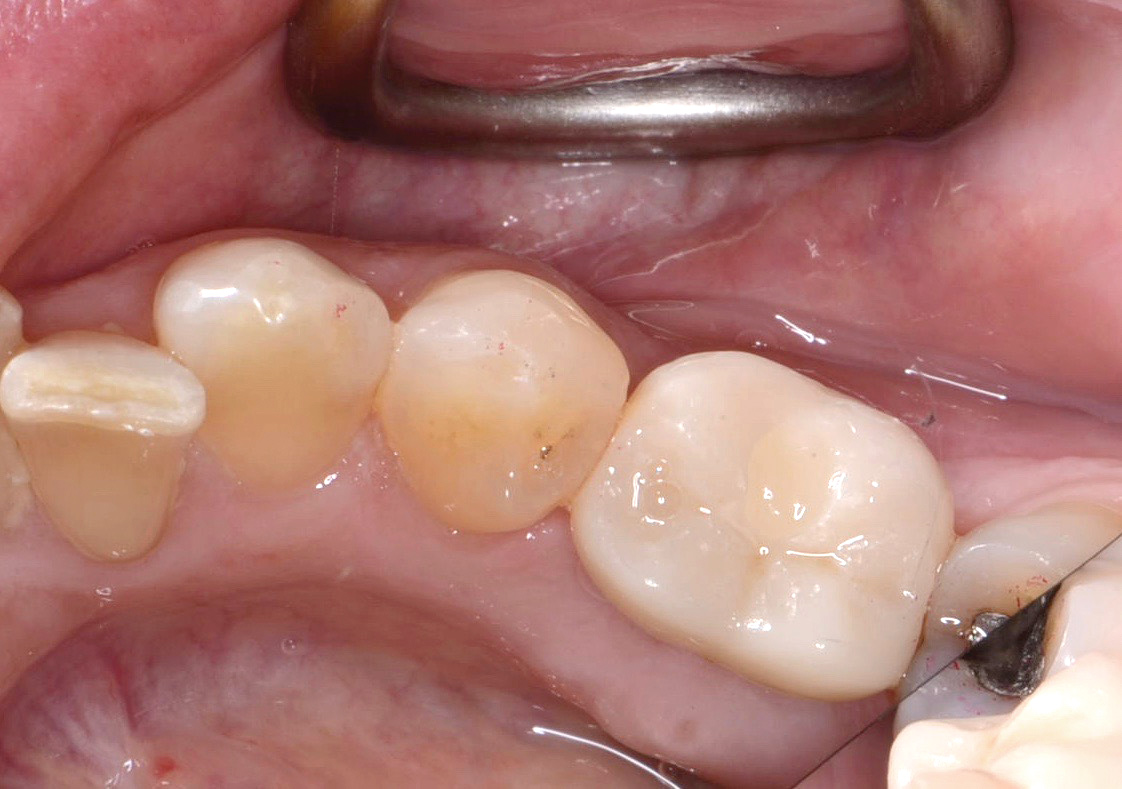

Fig 14. Clear resin cement left on the implant abutment.

Figure 14

Fig 15. Implant abutment following cement removal.

Figure 15